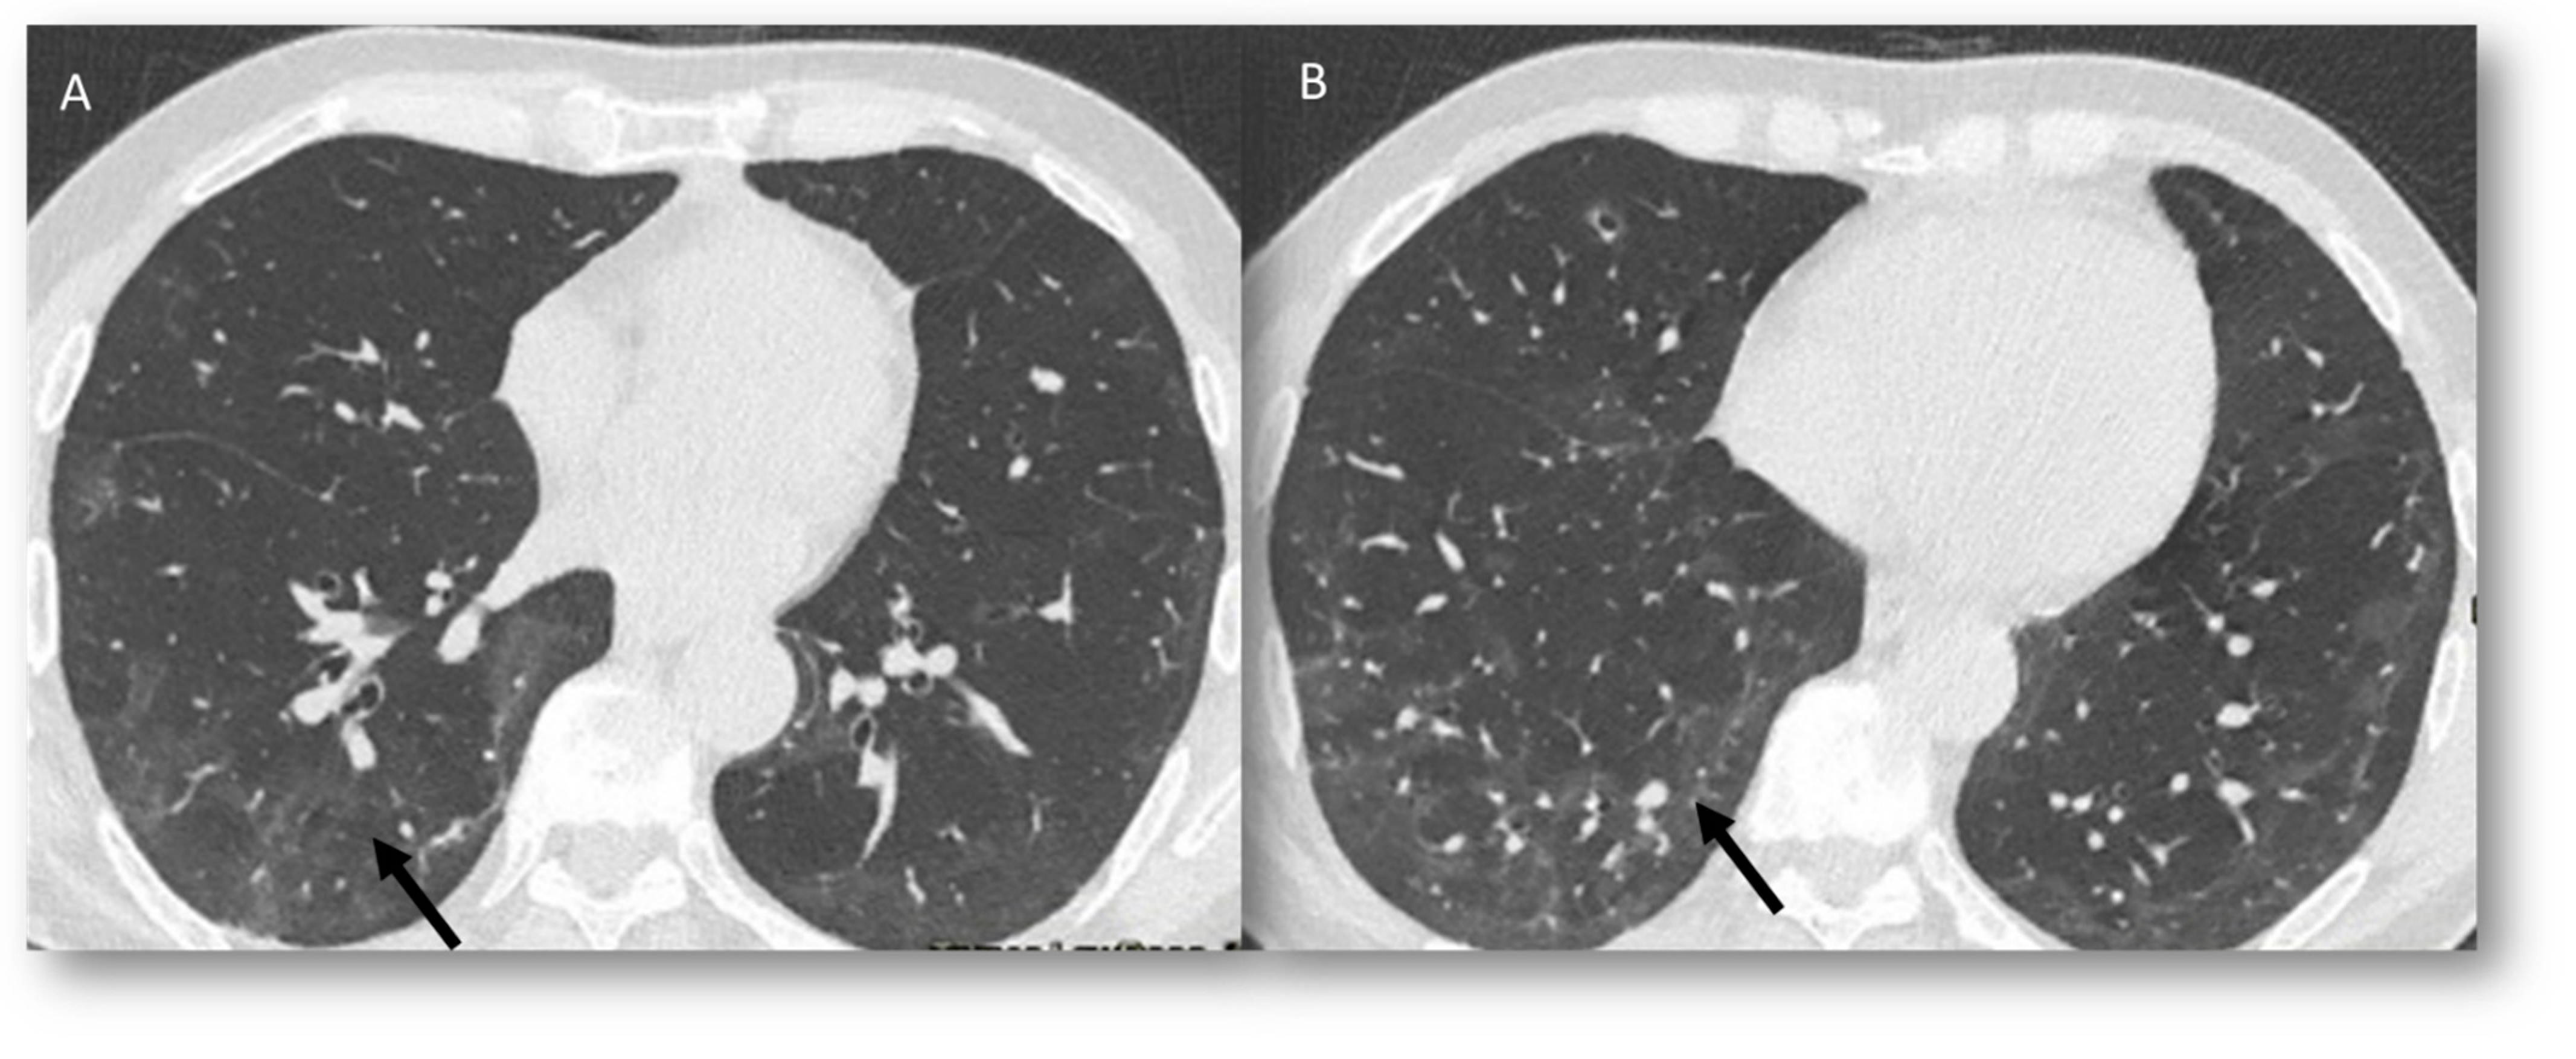

| RRP | Target area | Ground-glass opacities and consolidative opacities. | Unknown (A non-immune fixed drug reaction-like condition, dysregulated release of reactive oxygen species, abnormalities of tissue vasculature and impaired DNA repair). |